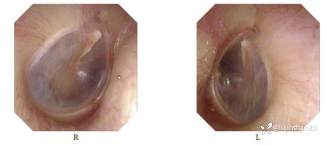

体格检查:耳:双耳廓无畸形,双外耳道无异常分泌物,双鼓膜完整,标志清,动度可。音叉试验(C256):WT偏左,RT双耳(+)。